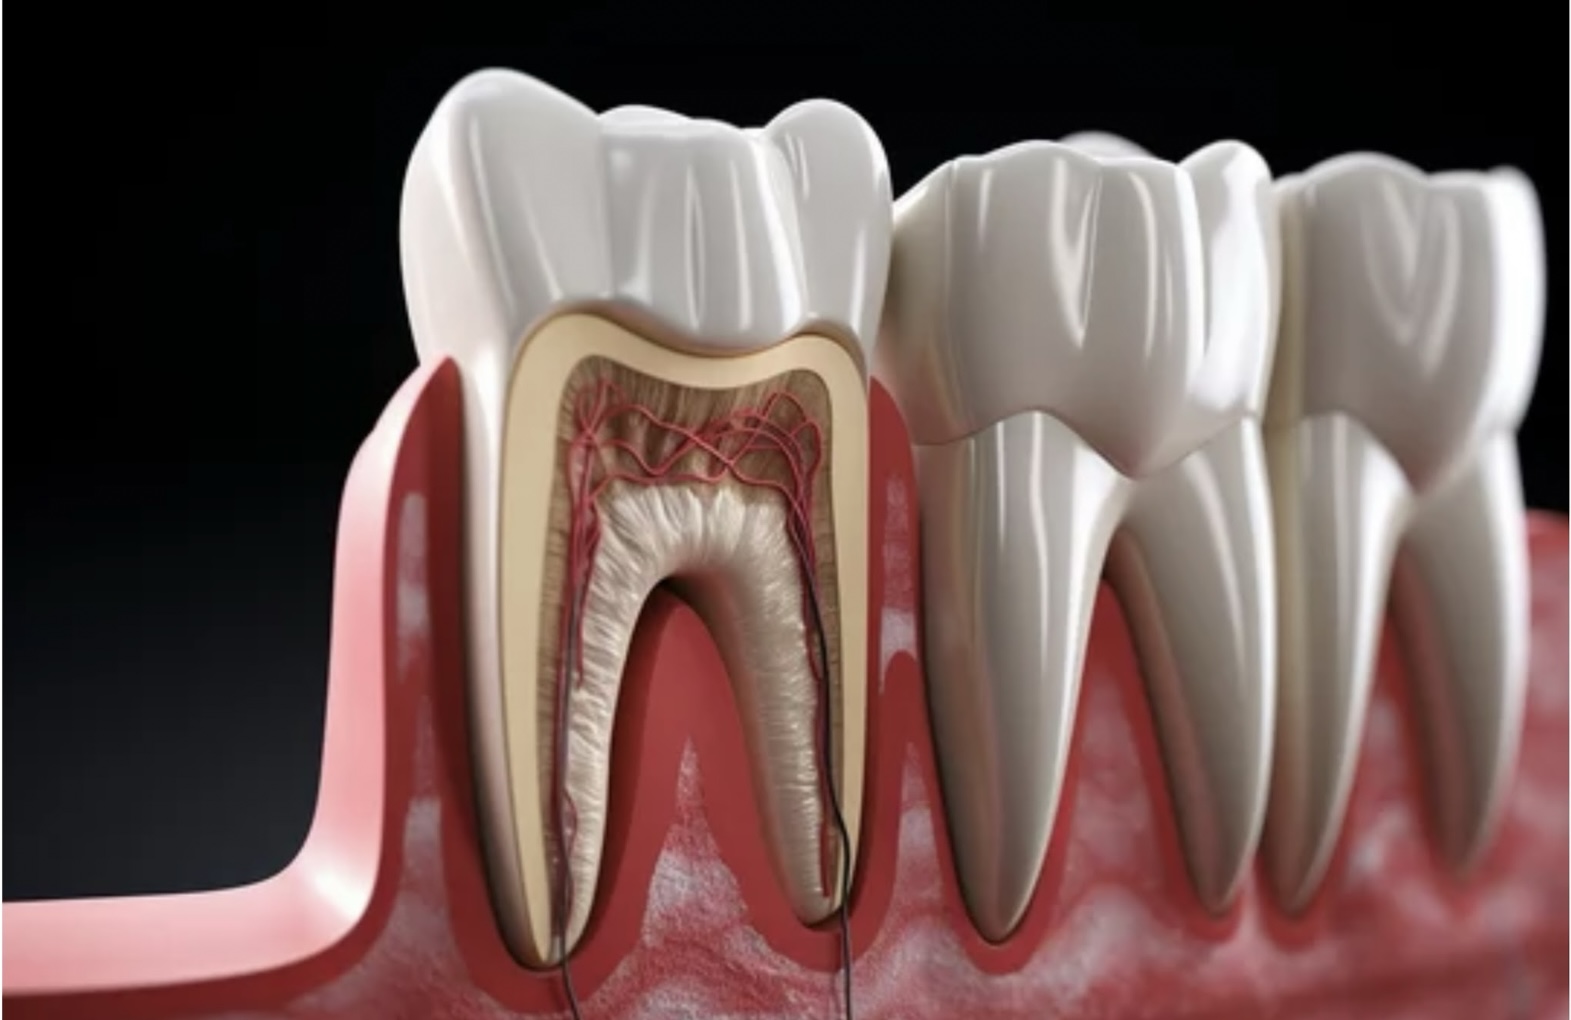

歯の神経の役割

そもそも歯の神経にはどんな役割があるでしょうか?

・歯に栄養を与える

・痛みや刺激を伝える

・細菌をやっつける

などの役割があるので、神経を取った歯は栄養がいかなくなり枯れ木のように脆くなってしまいます

歯の根の治療とは

歯の神経までむし歯が進行している歯は、歯の内部の「根管」と呼ばれる神経の詰まった管の奥までむし歯菌が侵入しています

そのため、細菌感染した神経を可能な限り取り除かなければならないのです

除去した後は、細菌が再び入り込まないようにきっちり封鎖することも重要です

②精密な処置が必要

ダメになった神経の除去は精密な作業です

ファイルという細長い器具を神経のお部屋に挿しこみ、可能な限り神経を除去していきます

歯の根っこはそれぞれ違うので、本数や形によっても難易度が変わります

例えば前歯は根管が1本ですが大臼歯と呼ばれる奥歯は根管が何本もあります

また、根管の形が曲がっていたり、枝分かれしている歯もあります

そういった歯には器具が入りにくく、1回では根管内の神経を全て除去するのは難しいのです